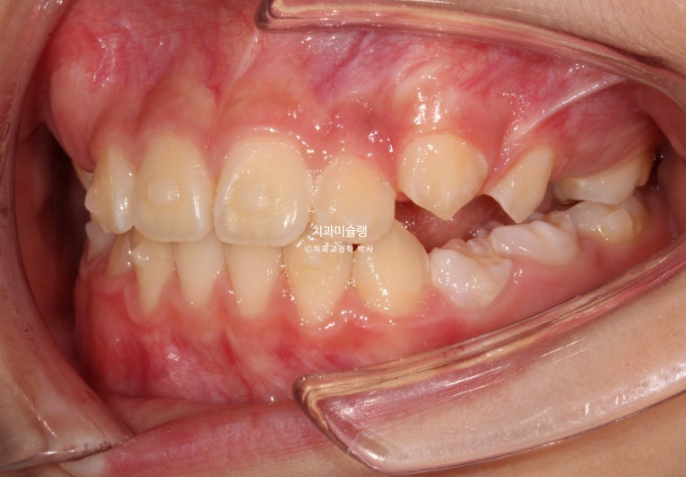

24년 11월까지 약 9개월간 첫세트의 46개 장치를 모두 낀 후 모습입니다.

24.11

중심선은 잘 맞으며 깊게 물리던 과개교합이 개선되었습니다.

그 사이 유치 송곳니와 유치 어금니가 빠지고 영구치들이 내려오네요.

이제 막 나오고 있는 파란화살표 치아는 썩은게 아니라 선천적으로 법랑질저형성을 보이는 치아입니다.

기능에는 지장 없습니다.

인비절라인퍼스트 치료에서 앞니 4개의 배열과 영구치 나올 공간 확보는 기본입니다만

사진처럼 송곳니의 경우 공간이 충분히 확보되어도 막상 나올 때는 약간 덧니처럼 나오는 경우가 꽤 있습니다.